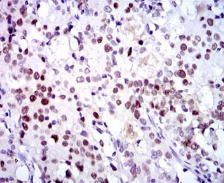

IHC    1/200 - 1/1000